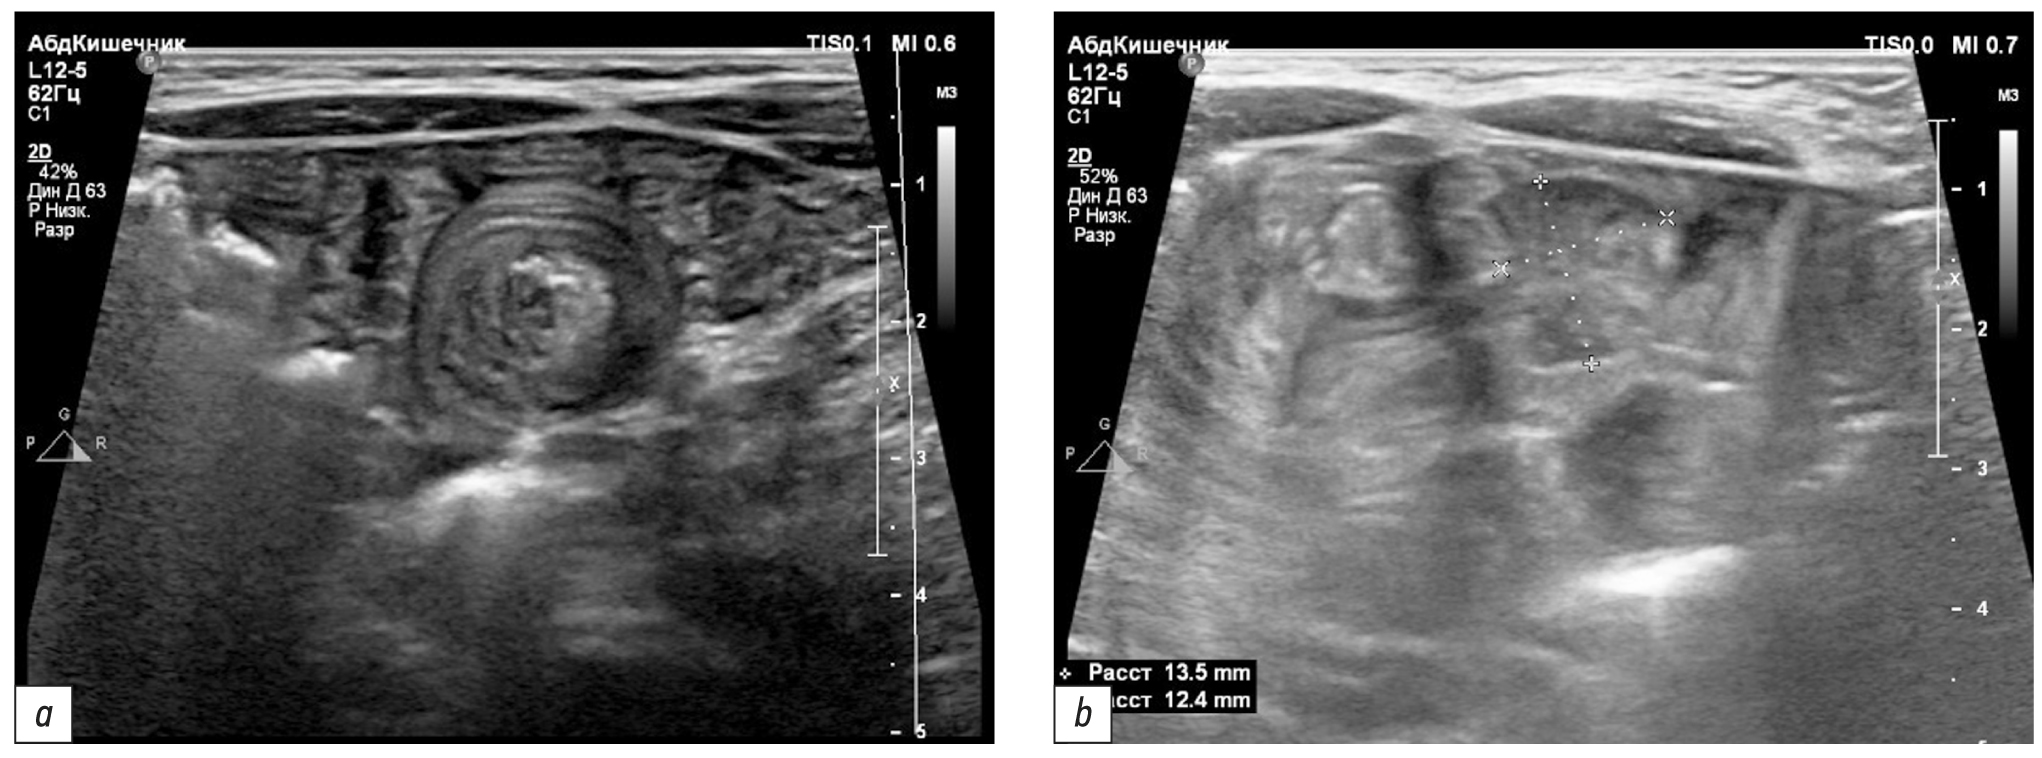

Поиск источника скрытого кровотечения был продолжен УЗИ ОБП, при котором была выявлена транзиторная тонкокишечная инвагинация (множественные нестабильные мишенеподобные образования около 20 мм в диаметре). При повторном УЗИ ОБП на фоне транзиторных тонкокишечных инвагинатов в мезогастрии было визуализировано стабильное образование (полип кишечника?), размерами 16×21 мм без чёткой анатомической локализации (рис. 4). Повторное эндоскопическое исследование верхних и нижних отделов кишечника в пределах досягаемости (исследование толстой кишки с осмотром около 40 см подвздошной кишки, ЭГДС с осмотром около 40 см тощей кишки) не дало новых результатов. При этом у ребёнка сохранялись симптомы скрытого кишечного кровотечения в виде мелены и железодефицитной анемии. Для исключения кровотечения из верхних дыхательных путей ребёнок был консультирован оториноларингологом, с помощью ультратонкого эндоскопа был выполнен осмотр носовых ходов, носоглотки и гортани — следов крови и потенциальных источников кровотечения выявлено не было.

Рис. 4. Сонограммы: a — транзиторный тонко-тонкокишечный инвагинат, b — солидное образование размерами 16×21 мм

Fig. 4. Sonograms: a — transient small bowel intussusception, b — solid lesion 16×21 mm in size